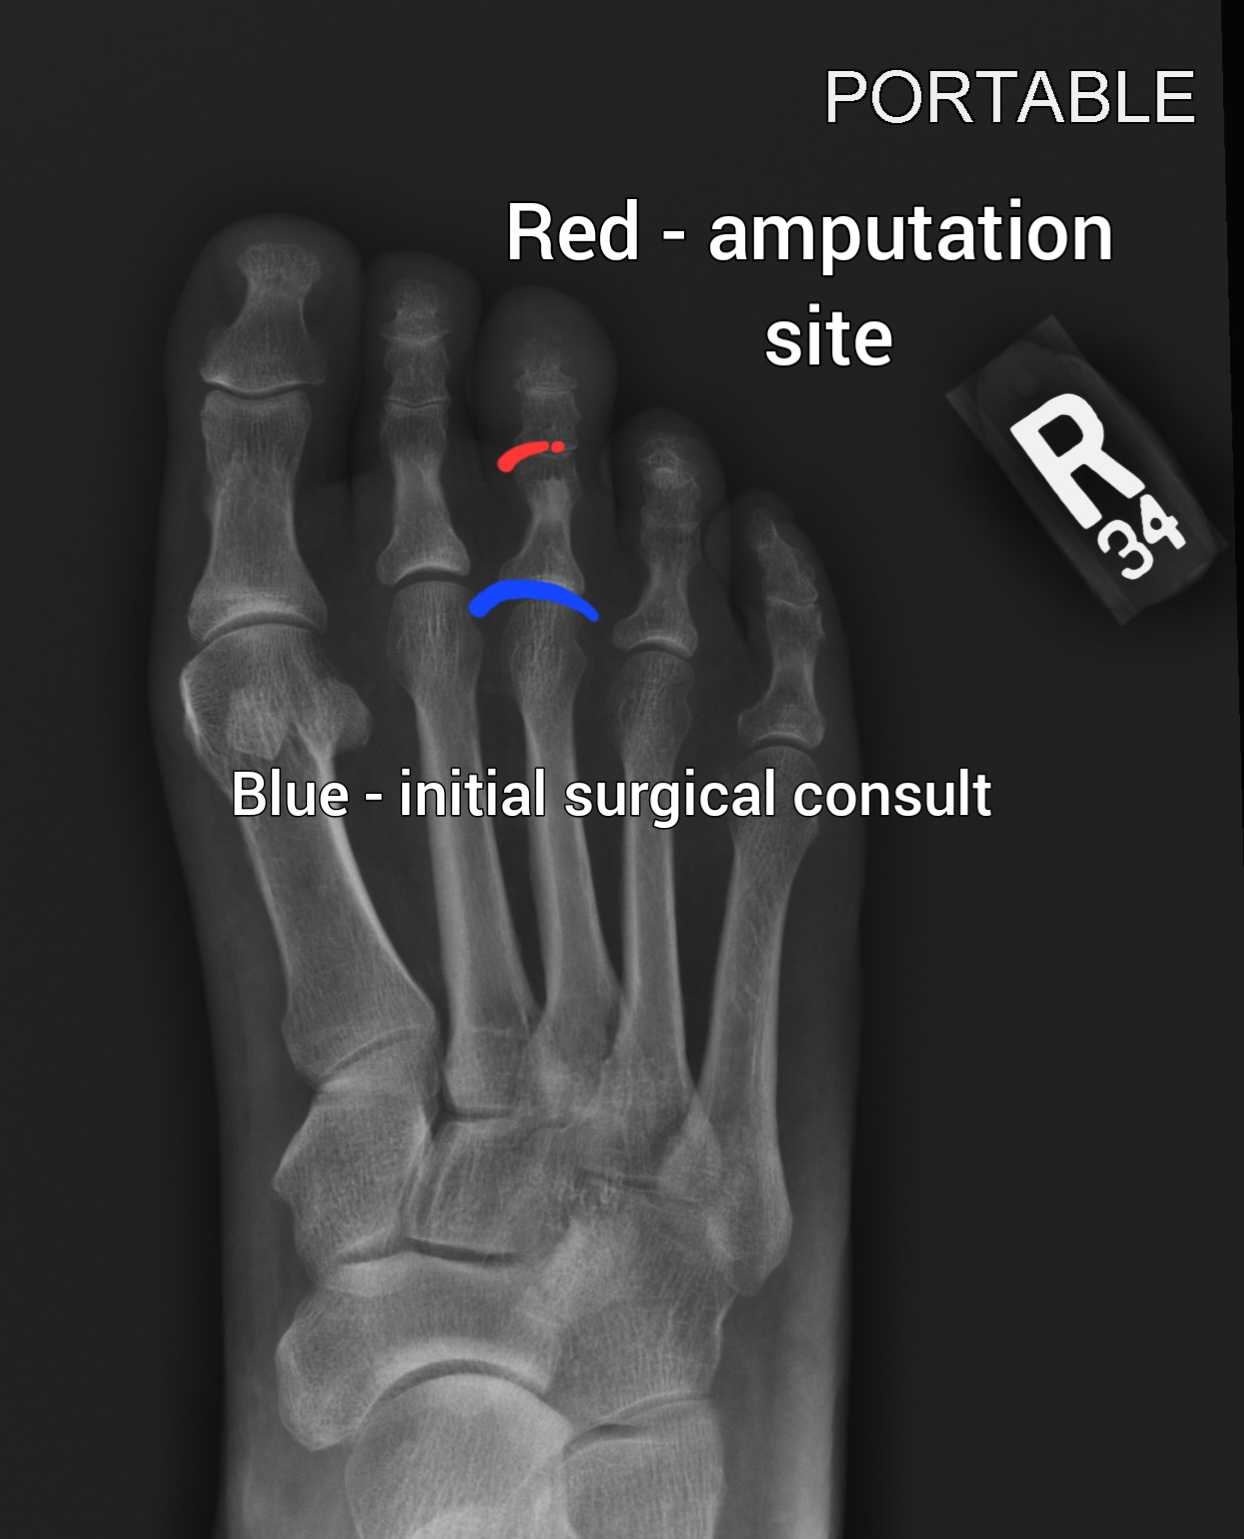

I was diagnosed with Type 2 diabetes in February and I have been walking to decrease weight gain and increase my physical activity. I developed a blister of the middle toe on my right foot, and even though I was caring for the blister as directed by my doctor, the infection was hiding under a callus, and traveled to the bone and it has begun to kill the tissue of my toe, so the surgeon is going to amputate it in the next 48 hours. I am hopeful that the infection has not spread further into my foot, and more surgery is not needed.